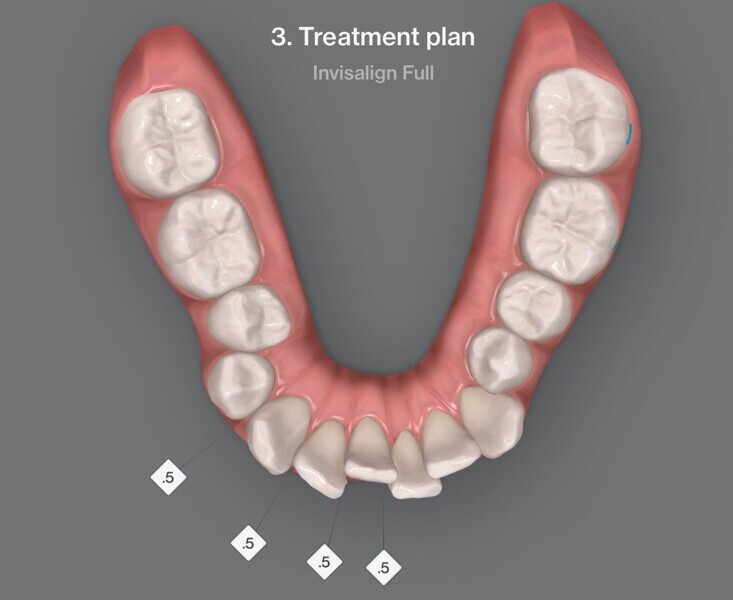

Le premier plan de traitement par simulation ClinCheck prévoit 53 aligneurs, afin de réaliser une distalisation séquentielle postérieure d’environ 4 mm sur le côté gauche du maxillaire, une expansion de 2 mm par quadrant et un alignement dans la zone antérieure. Il prévoit également une réduction interproximale (RIP) sélective de 0,25 mm sur chaque face des dents de l’arcade mandibulaire, et de 0,10 mm à 0,15 mm pour les dents de l’hémiarcade maxillaire droite (Fig. 4). Une application topique de fluorure est planifiée dans les zones soumises à une RIP après la procédure. Des élastiques de classe II sont utilisés du côté gauche pour faciliter la distalisation. La fréquence de changement des aligneurs est fixée à sept jours et elle sera ramenée à cinq jours par la suite. Un accélérateur de traitement orthodontique par vibrations est utilisé, afin d’augmenter la vitesse et la prédictibilité des mouvements dentaires. Le traitement n’envisage pas l’utilisation d’aligneurs de surcorrection.

Fig. 4a : Premier résultat prévu par simulation ClinCheck.

Fig. 4b : Premier résultat prévu par simulation ClinCheck.

Fig. 4c : Premier résultat prévu par simulation ClinCheck.

Fig. 4d : Premier résultat prévu par simulation ClinCheck.

Fig. 4e : Premier résultat prévu par simulation ClinCheck.